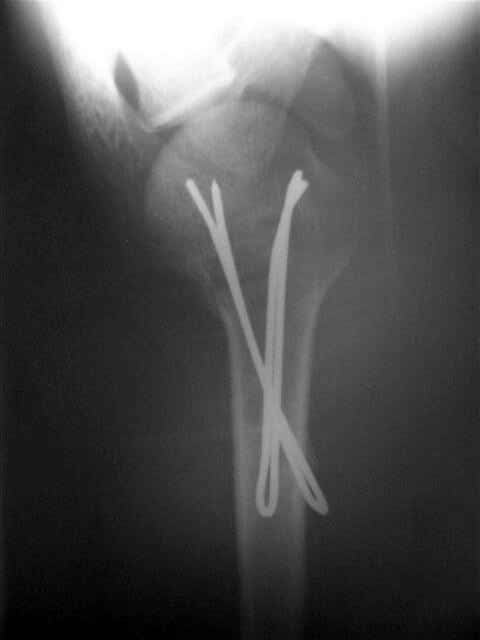

Re: Перелом шейки плеча

Посылаю послеоперационные Рг граммы.